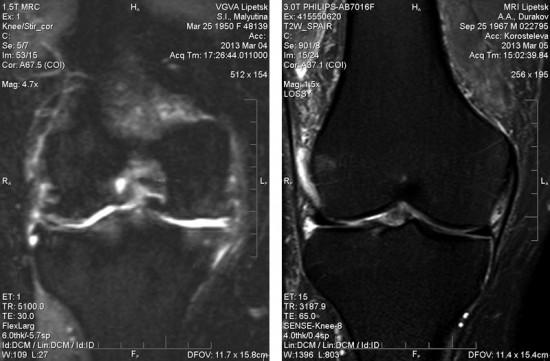

МРТ (магнитно-резонансная томография) – безопасный, высокоинформативный метод диагностики различных заболеваний суставов, требующий современного оборудования и высококлассных специалистов.

Чем более мощный томограф, тем более мелкие структуры организма видны. Соответственно, тем меньше вероятность пропустить проблемный участок и выше достоверность исследования.

Современный мощный томограф от качественного производителя дает возможность построения трехмерной модели сустава. На таком изображении, полученном в ходе МРТ, можно рассмотреть мягкие ткани, хрящи, связки, кровеносные сосуды, нервные стволы.Это позволяет доктору поставить верный диагноз и назначить правильное лечение, а пациенту – во многих ситуациях избежать операции.

МРТ – один из самых точных и достоверных методов современной медицинской диагностики, в том числе и в ортопедии. При постановке диагноза врач всегда руководствуется клиническими данными, при необходимости прибегает к рентгенологическим методикам или УЗИ. В сложных случаях возможно использование МРТ как дополнительной методики для уточнения диагноза. Особенно когда стоит вопрос об оперативном лечении. При проведении магнитно-резонансной томографии врач получает возможность не только исследовать структурные и патологические изменения, но и оценить патофизиологические процессы в суставе в целом или его отдельных структурах. Залогом успеха обследования и, как следствие, лечения являются использование современных и мощных аппаратов, высокий уровень подготовки специалистов МРТ и их тесное сотрудничество с лечащим врачом-ортопедом.